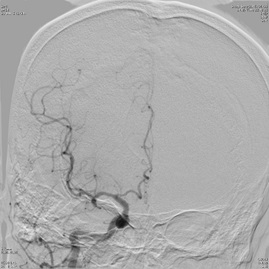

脳卒中担当医が常に診察することで、rt-PA 静注療法、脳血管内手術、脳神経外科手術の必要性を適切に判断し常に施行可能な体制を整えています。(写真は脳血管内治療の様子)

脳血管内治療1

脳血管内医療2